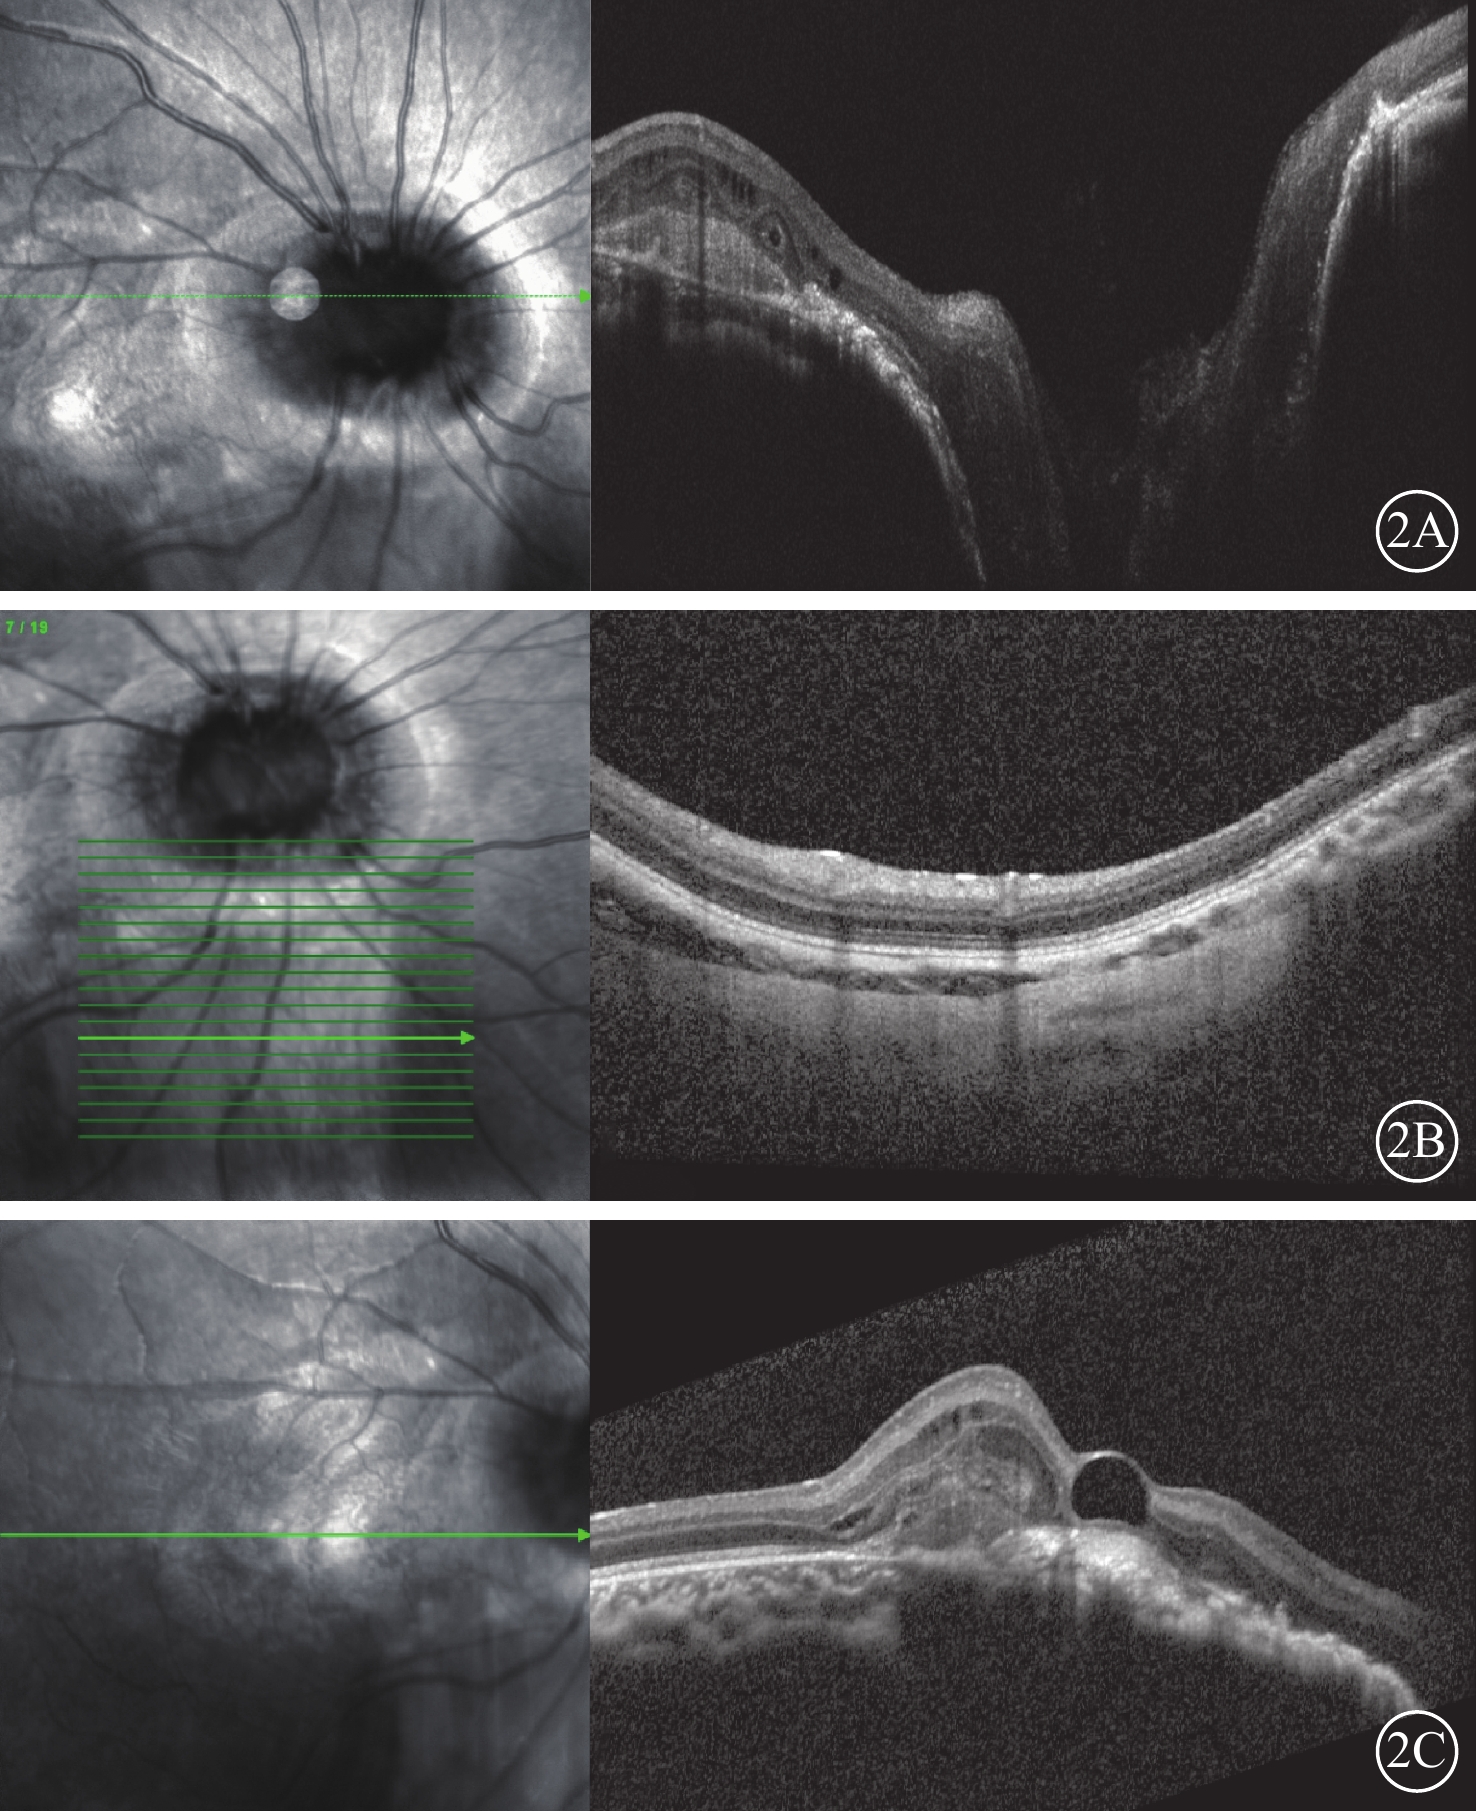

患兒男,3歲。因體檢發現右眼眼底異常于2018年8月21日至溫州醫科大學附屬眼視光醫院杭州院區就診。患兒足月順產,否認吸氧史、家族史;父母非近親結婚;母親無孕期疾病史或特殊用藥史。全身檢查:顱腦CT及MRI檢查未見明顯異常。眼部檢查:右眼視力+2.00/-2.00×25→0.05,左眼視力+2.00/-0.75×180→0.7。雙眼眼壓指測Tn。雙眼眼前節未見明顯異常。右眼視盤增大,周邊呈粉紅色,中央有漏斗形深凹陷,底部被灰白色膠質樣組織填充,其邊緣不規則,且隆起似環形嵴,其上有色素沉著,嵴環外為視網膜脈絡膜萎縮區;視盤邊緣有約20支狹細血管,呈放射狀走行,爬出嵴環向四周視網膜分布,黃斑區可見灰白色病灶,呈瘢痕樣改變,視盤下方視網膜見橘紅色改變,透見脈絡膜血管。左眼視盤顏色淡、邊界清楚,呈橫橢圓形,C/D≈0.2,其邊緣視網膜血管分支稍增多,走行異常(圖1)。OCT檢查,右眼視盤深度凹陷,視盤上見異常物質,黃斑區視網膜下見中強反射灶,視網膜層間見弱反射暗腔,視盤下方(眼底彩色照相對應橘紅色區域)脈絡膜血管層萎縮變薄(圖2);左眼黃斑中心凹形態正常。B型超聲檢查,右眼視盤漏斗狀凹陷,其后回聲增強,黃斑區局部隆起(圖3)。FFA檢查,右眼早期擴大的視盤呈弱熒光,其周圍色素遮蔽呈弱熒光,外側不規則視網膜脈絡膜萎縮區呈強熒光環,視盤邊緣處血管數量明顯增多,周邊視網膜存在無灌注區,視網膜血管異常吻合,晚期視盤組織著染呈強熒光;黃斑區視網膜早期見強熒光,隨時間延長,滲漏逐漸明顯,范圍擴大。視盤下方早期輕度強熒光,晚期熒光明顯增強。左眼未見明顯熒光素滲漏(圖4)。診斷:右眼牽牛花綜合征(MGS)合并脈絡膜新生血管(CNV),右眼脈絡膜缺損。